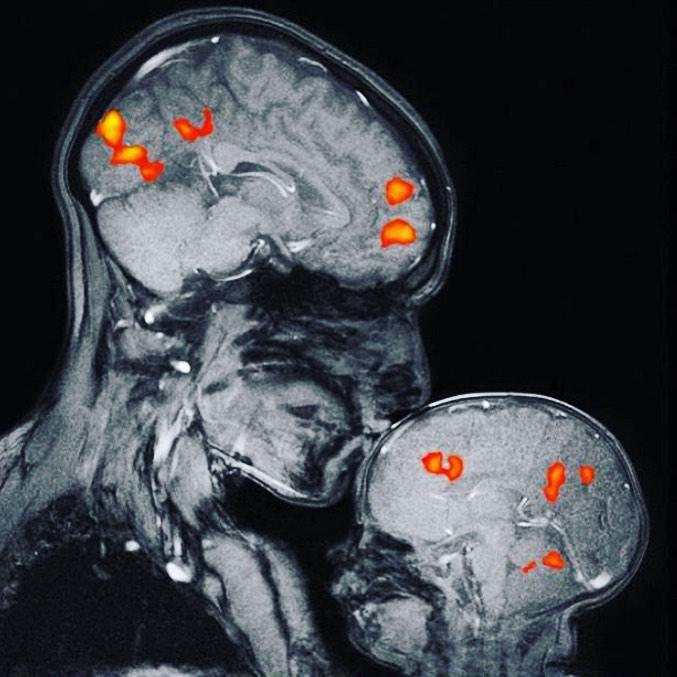

Neurologul Rebecca Saxe a prezentat cea mai frumoasă ”fotografie” a anului. De fapt, imaginea unei rezonanțe magnetice surprinsă în momentul în care o mamă își sărută fiul de numai două luni. Buzele puse pe căpșorul omulețului declanșează, imediat, în creierul acestuia, o reacție. Se eliberează dopamină, cea care ne dă senzația de bine, dar și ociticină, botezată ”hormonul iubirii”, pentru că este resposabilă cu afecțiunea și cu atașamentul

Într-o zi, a avut ideea de a realiza o rezonanță magnetică pentru a putea demonstra tuturor necredincioșilor că iubirea maternă este ”vizibilă” și că ea provoacă în creierul micuțului diferite reacții pozitive. Așa că ambii au intrat, în aprilie 2015, într-un tub ”Tesla 3”, preț de câteva minute.

Așa cum se poate vedea, creierul micuțului este puțin mai întunecat, lucru logic, dacă ne gândim că el deține o cantitate mai mică de substanță albă. Aceasta este alcătuită din mielină, un strat de fosfolipide, electroizolant, care înconjoară axonii neuronilor. Rolul este acela de a izola electric fibrele nervoase, prevenind pierderea impulsului electric de către axon, în drumul acestuia de la o celulă nervoasă la alta.

Sărutul provoacă o reacție chimică în creierul celui mic. Se declanșează o ”explozie” a oxitocinei, denumită ”hormonul iubirii”. Acesta reduce temerea și crește încrederea, stârnește sentimente de afecțiune și de atașament, semn că bebelușul a priceput că este protejat. De asemenea, se eliberează dopamină, cea care face să ne simțim bine și vasopresină, ”liantul” ce leagă mamele de bebeluși în primele luni de viață ale acestora. În fine, s-a semnalat și prezența serotoninei, cea care reglează starea noastră de spirit.